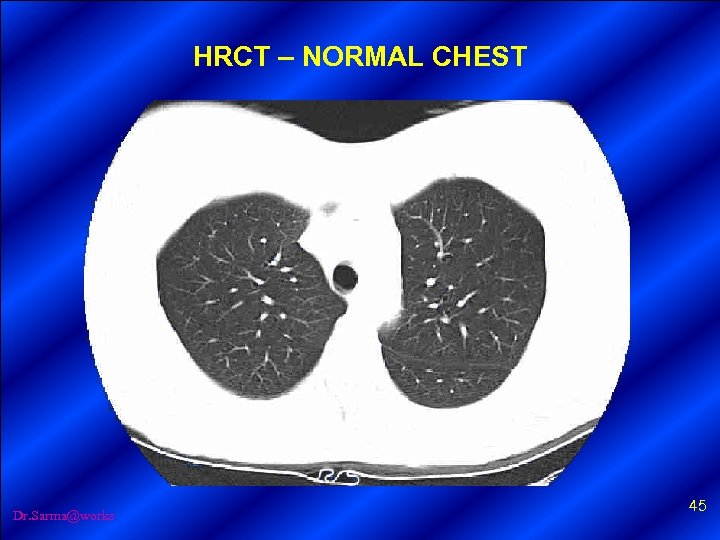

HRCT – NORMAL CHEST Dr. Sarma@works 45